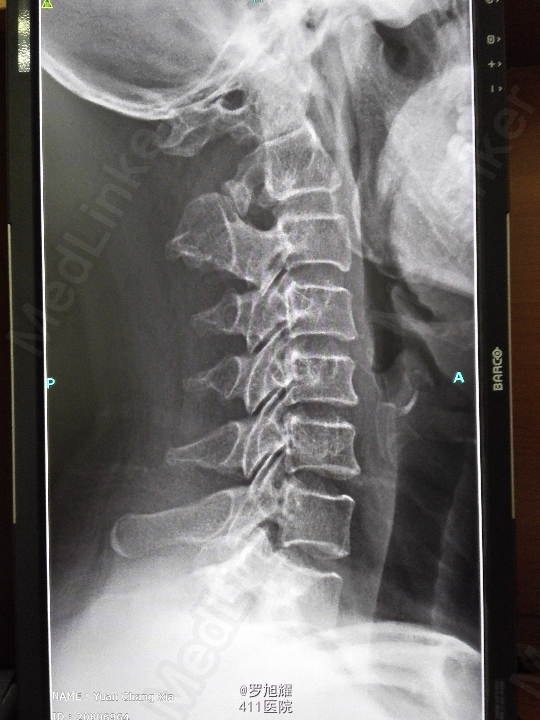

右侧躯体麻木1年,右上肢及下肢麻木2月余。 查体:颈椎活动受限,右上肢肘关节以远痛温觉减退,右侧胸4平面以下痛温觉及触觉减退,四肢肌力尚可,右侧霍夫曼征阳性,右侧上下肢所有腱反射亢进。 颈椎X线示:颈2椎板棘突缺如,颈3棘突肥大增高。 颈椎CT示:颈2椎板棘突缺如,颈3棘突肥大增高,颈2/3椎间盘突出,左侧颈2残留部分椎板进入椎管。枢椎齿突增生,寰枢关节退变。 颈椎MRI示:颈2/3椎间盘突出,左侧颈2椎板进入椎管,颈髓受压变性。

查体:颈椎活动受限,右上肢肘关节以远痛温觉减退,右侧胸4平面以下痛温觉及触觉减退,四肢肌力尚可,右侧霍夫曼征阳性,右侧上下肢所有腱反射亢进。 颈椎X线示:颈2椎板棘突缺如,颈3棘突肥大增高。 颈椎CT示:颈2椎板棘突缺如,颈3棘突肥大增高,颈2/3椎间盘突出,左侧颈2残留部分椎板进入椎管。枢椎齿突增生,寰枢关节退变。 颈椎MRI示:颈2/3椎间盘突出,左侧颈2椎板进入椎管,颈髓受压变性。